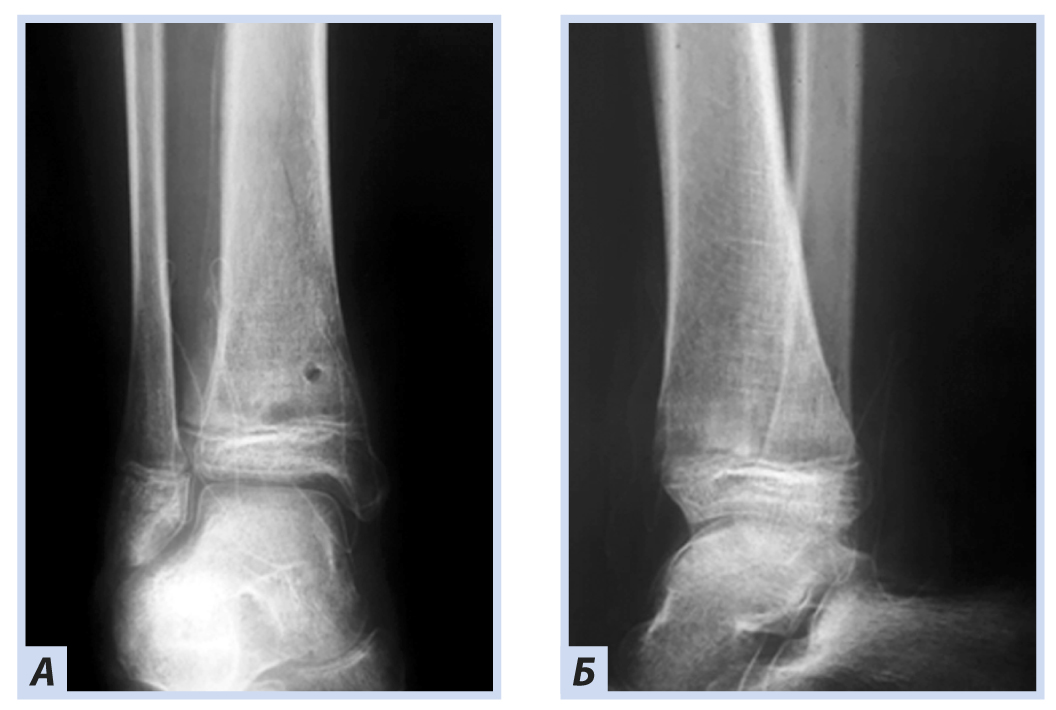

Клиническое наблюдение 1

Девочка, 10 лет, диагноз: «Закрытый дистальный остеоэпифизеолиз правой большеберцовой кости, Salter–Harris, II тип». Травму получила, упав с самоката, вследствие чрезмерного сгибания стопы кзади. По механизму травмы — ротационно-флексионный перелом дистального отдела костей голени. По данным компьютерной томографии выявлена значительная степень (5 мм) смещения отломков. Учитывая возраст больной, остеосинтез выполнен закрыто перекрещивающимися спицами. Дополнительная иммобилизация осуществлялась в задней гипсовой лонгете до коленного сустава. Контрольные рентгенограммы выполняли через 4 и 6 нед. после репозиции. Спицы удалены через 6 нед., конфигурация сустава восстановлена полностью (рис. 1–5).

Рис. 1. Девочка, 10 лет. Рентгенограммы дистального отдела костей правой голени. Дистальный остеоэпифизеолиз правой большеберцовой кости, Salter–Harris II тип: А — прямая проекция; Б — боковая проекция.